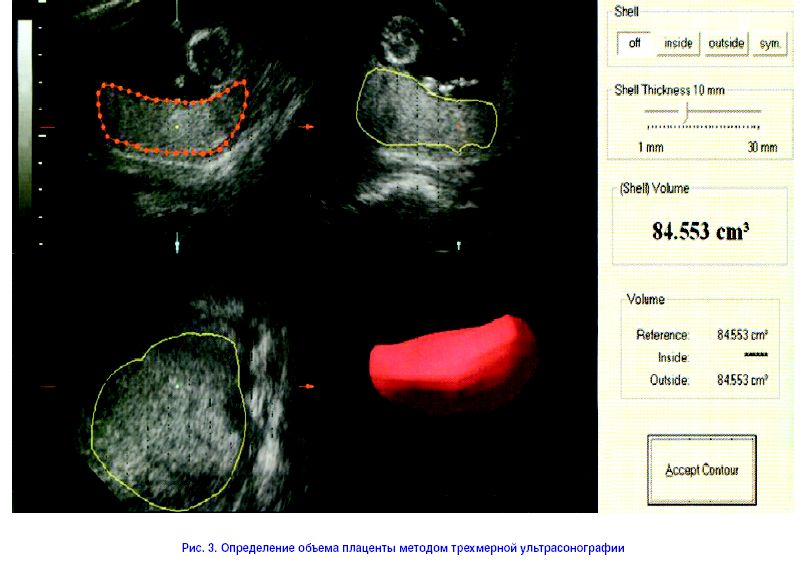

С недавних пор появилась возможность оценивать объем и рост плаценты в период беременности методом трехмерной ультрасонографии (рис. 3). Объем плаценты увеличивается со средней величины около 16 мм на 10-й неделе до 200 мм на 23-й неделе беременности. Следовательно, соотношение между массой плода и плаценты на 23-й неделе приблизительно равно 2, а к концу нормальной беременности – около 6. Любопытен тот факт, что у 17 плодов с хромосомной аномалией (трисомия 21 пары) отмечено уменьшение объема плаценты по сравнению с нормальными плодами аналогичного гестационного возраста (рис. 4). В исследованиях, проведенных во время родов, установлено, что для недоношенных новорожденных объем плаценты и соотношение масса тела/плаценты были меньше, чем у детей с той же массой тела, родившихся в срок [19]. Предварительные данные свидетельствуют о том, что если при нормальной беременности сниженная масса плаценты не ассоциируется со значительным уменьшением массы тела плода, то при беременности, протекающей с IUGR, существует отчетливо выраженная связь между сниженной массой плаценты и дефицитом массы плода, особенно в наиболее тяжелых случаях IUGR. С другой стороны, снижение массы плаценты и значения плодно/плацентарного весового соотношения описано при беременности, осложненной гестационным сахарным диабетом [23], причем даже при обеспечении оптимального уровня гликемии у матери на протяжении всего третьего триместра [24]. Следовательно, есть основания полагать, что объем плаценты, измеренный во втором триместре беременности, будет достоверно коррелировать с массой новорожденного [25, 26].